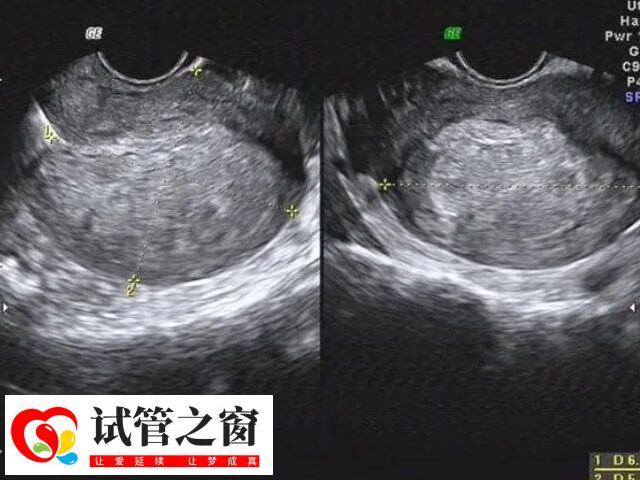

輸卵管積液是指在輸卵管內部出現滲漏或堵塞,造成腔道內液體無法正常排出而引起的疾病。當存在輸卵管積液時,女性可能會感到腹痛或不適,并且容易對試管移植造成影響,對此如何處理輸卵管積液,如下所示: